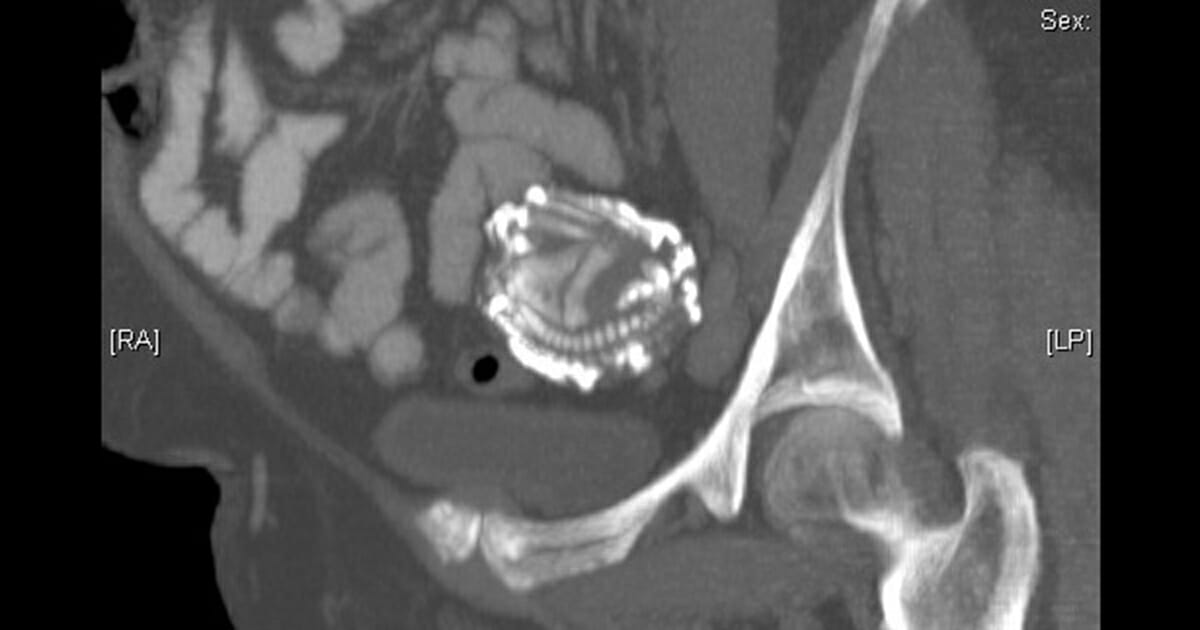

Fenomenet lithopedion är extremt ovanligt och innebär att ett större foster avlider utanför livmodern, ett så kallat utomkvedshavandeskap. Fostret blir kalcifierat för att skydda modern från förruttnelsen.

Fostret hade utvecklats utanför livmodern och blev sedan en främmande kropp för moderns immunsystem. Därför bildade kroppen ett skal av calcium runt det – varför fenomenet kallas ”stenbebis” eller ”stone baby” på engelska. Skalet hade blivit större och starkare med åren, för att skydda kvinnan från infektioner.

Foto: Youtube / The 46 year pregnancy